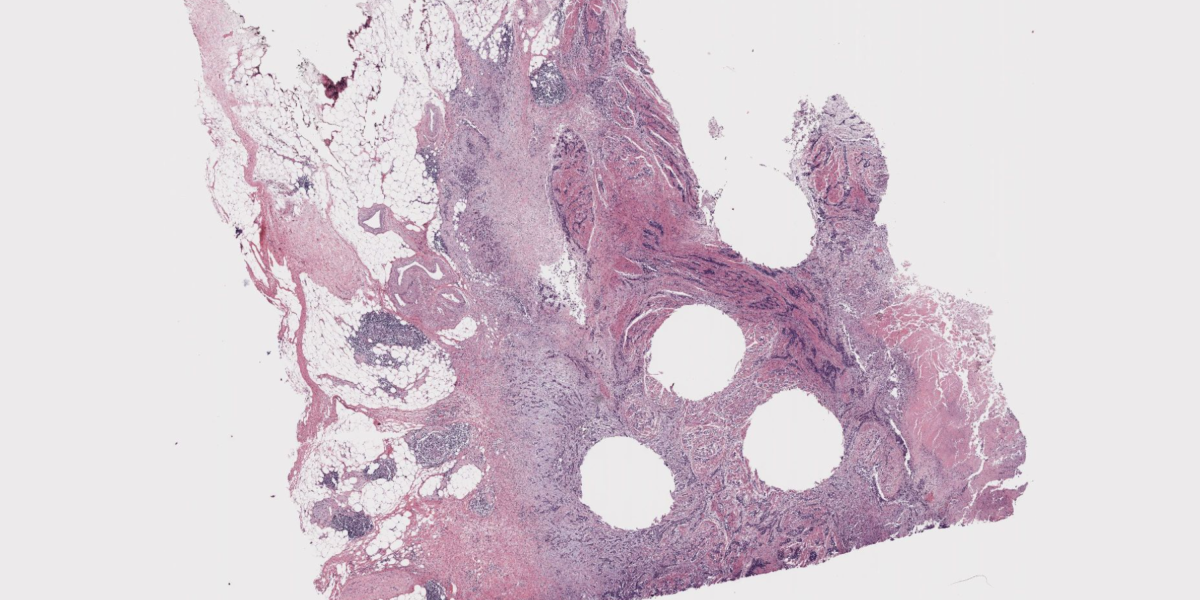

Finding and diagnosing cancer is all about spotting patterns. Radiologists use x-rays and magnetic resonance imaging to illuminate tumors, and pathologists examine tissue from kidneys, livers, and other areas under microscopes. They look for patterns that show how severe a cancer is, whether particular treatments could work, and where the malignancy may spread.

Visual analysis is something that AI has gotten quite good at since the first image recognition models began taking off nearly 15 years ago. Even though no model will be perfect, you can imagine a powerful algorithm someday catching something that a human pathologist missed, or at least speeding up the process of getting a diagnosis.

We’re starting to see lots of new efforts to build such a model—at least seven attempts in the last year alone. But they all remain experimental. What will it take to make them good enough to be used in the real world? Read the full story.